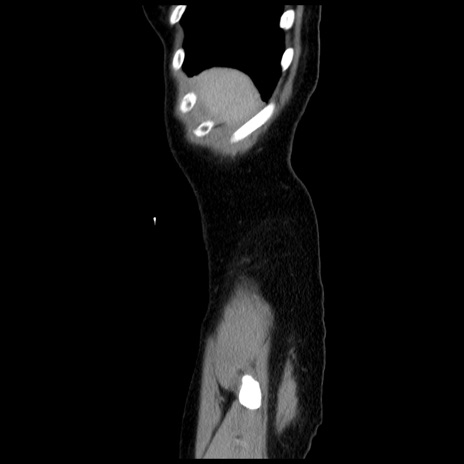

症例10(矢状断像)

【症例】 50歳代女性

【主訴】 腹痛

【現病歴】前日生レバーを食べた。今朝に排便あり。 昼前に突然発症の腹痛を生じ、当院救急外来を受診した。

【既往歴】 子宮筋腫にてで子宮全摘後

【身体所見】 意識清明、腹部:平坦、軟、下腹部やや左を中心に圧痛・反跳痛あり、筋性防御あり

【データ】WBC 7800、CRP 0.07